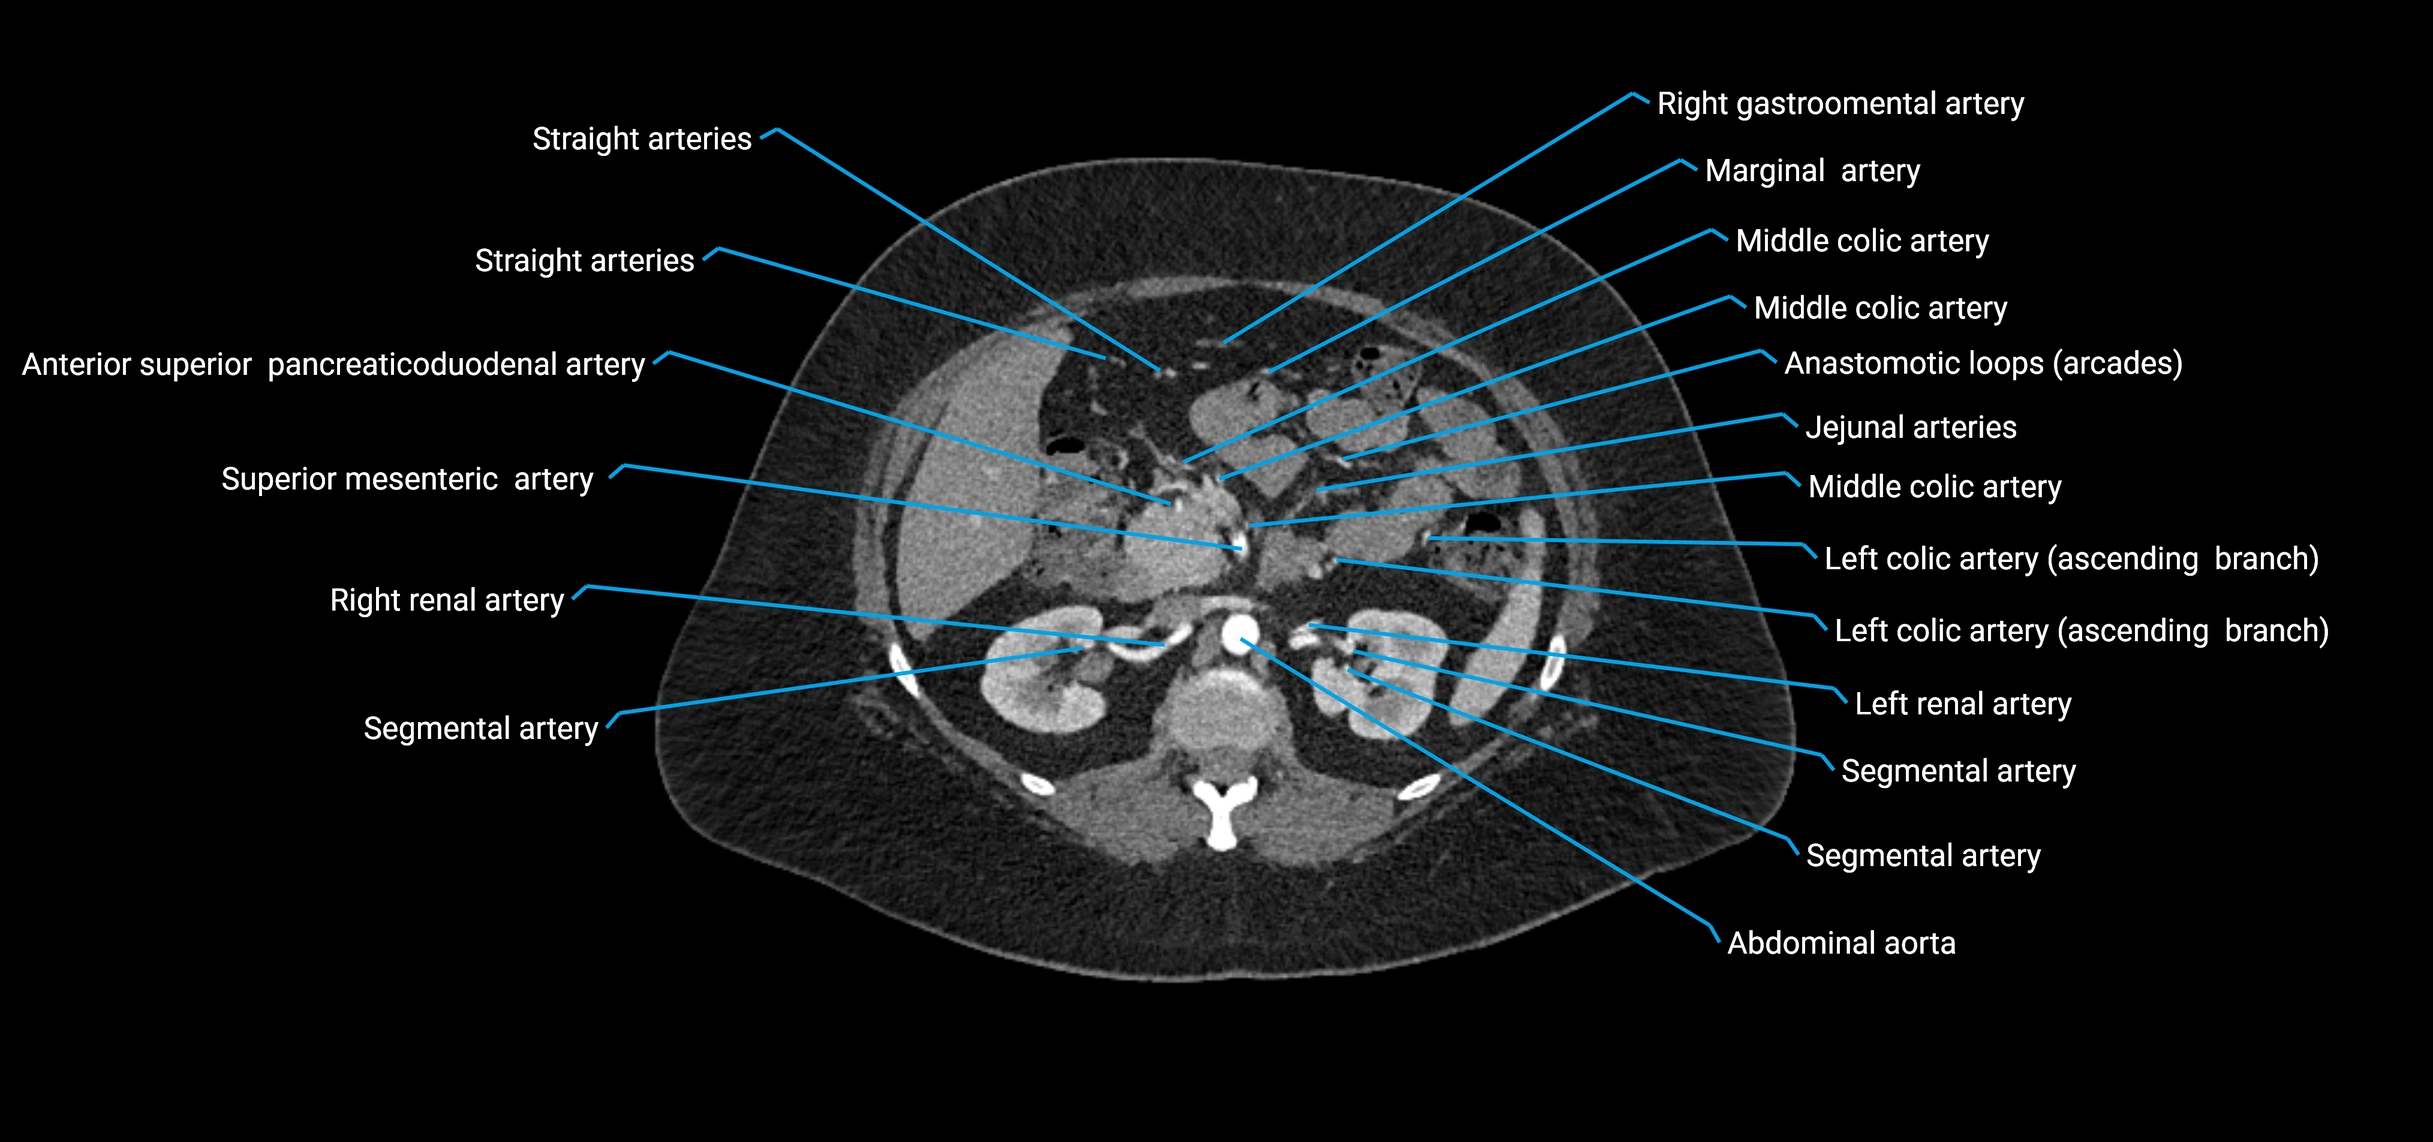

Contrast-enhanced CT (CTA):

• Gold standard for abdominal aortic imaging

• Provides excellent detail of lumen, wall, aneurysm, thrombus, and branch vessels

• Multiplanar and 3D reconstructions help in aneurysm measurement, stent graft planning, and dissection evaluation